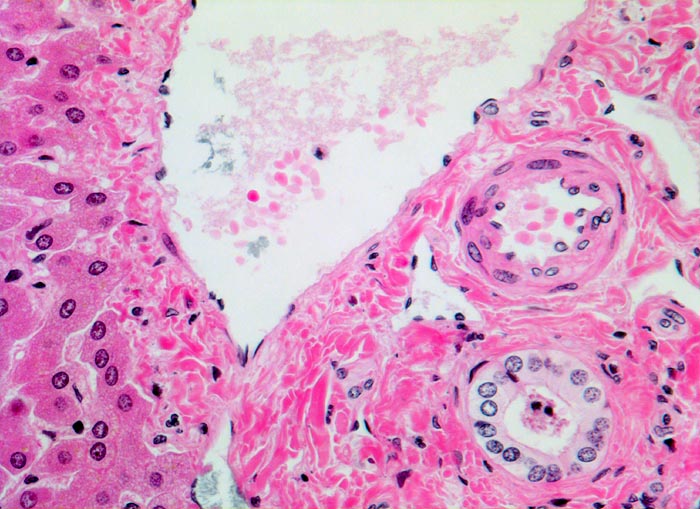

Anschnitt eines Portalfeldes mit Portalvenenast, Arterienast und Gallengang. Der Gallengang hat etwa dasselbe Kaliber wie die Arterie. Portalfeld ohne nennenswertes Entzündungsinfiltrat und ohne Fibrose. Links im Bild wenig unauffälliges Leberparenchym.